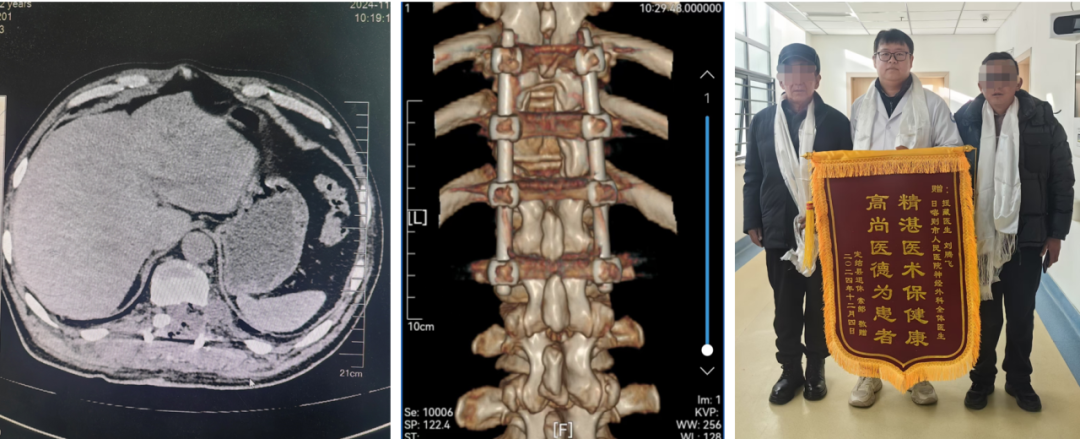

术后患者恢复非常好,术前症状完全消失,并无新发神经功能障碍。立竿见影的手术疗效,让患者及家属惊喜不已。术后复查胸椎X片及CT三维重建显示:内固定良好,肿瘤无残留。患者及家属对手术效果非常满意,对医院多学科诊疗团队的精湛技术和护理关怀感激不尽,出院时特地赠送锦旗表达感谢之情。

术后CT提示:肿瘤全切除,脊柱内固定良好